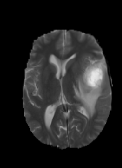

The dataset’s MR images are preprocessed so that the skulls and neck regions are removed. The images are aligned and co-registered to correct any head tilt or mismatches between MR modalities. Each voxel in the image corresponds to of brain tissue. Figure 5 illustrates a 2D axial input MR Images sample and the corresponding ground truth. The input images (a-c) show the different MR modalities: FLAIR, T1CE, and T2 images. The ground truth consists of peritumoral edema (ED) marked in light grey given by an intensity value of , enhancing tumor (ET) represented as a white region with as an intensity value, and the non-enhancing tumor (NET) and necrotic core region (NCR) as dark grey with an intensity value of . The models are evaluated as enhancing tumor (ET), tumor core (TC), and whole tumor (WT). The tumor core corresponds to NET/NCR and the enhancing tumor region. The whole tumor corresponds to all three tumor regions put together. The research aims to learn the ED, NET/NCR, and ET regions.